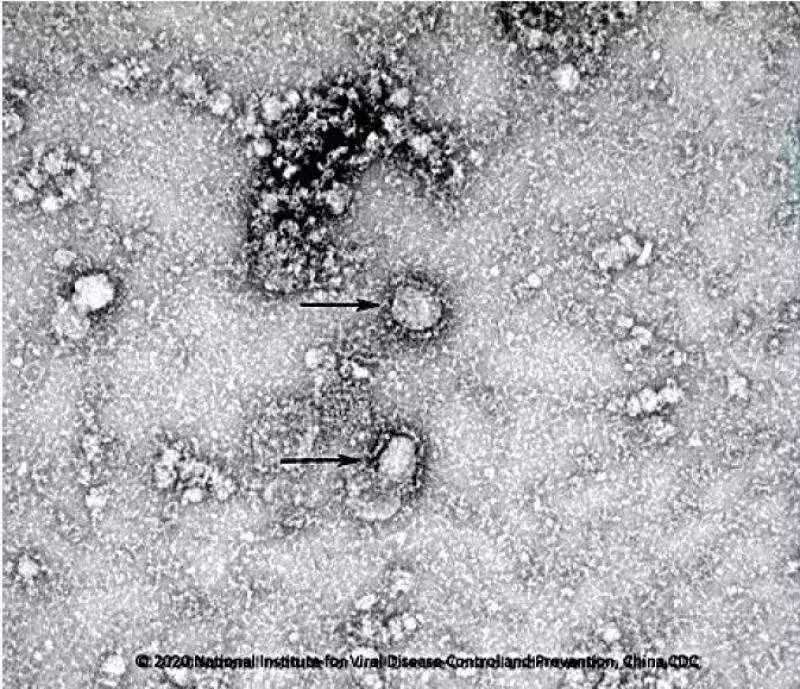

中国疾控中心已成功分离我国首株新型冠状病毒毒种。图片来自国家微生物科学数据中心网站